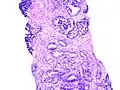

Die Einteilung umfasst ursprünglich fünf Grade, welche sowohl die Form, als auch die Anordnung der Drüsen beschreibt. Die Grade 1 und 2 sollen jedoch nicht mehr vergeben werden.[2] Grad 3 beschreibt kleine ungleichmäßige Drüsen, Grad 5 beschreibt die am schlechtesten differenzierten Tumoren, deren Wachstumsmuster fast jede Ähnlichkeit mit normalem Prostatagewebe verloren haben, Grad 4 liegt dazwischen.[3]

Gleason Grad 3 und 4 -

Gleason Grad 5